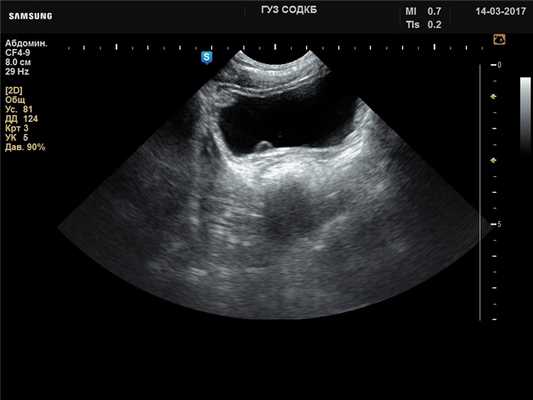

Мочевой пузырь - уретероцеле, B-режим

[EN] Эхограмма №728: «Пульсирующее» уретероцеле справа у мальчика 6 лет. Микроконвексный датчик 4-9 МГц (неонатальный), B-режим.

Автор: Суханов С.А., Саратов.

Изображение получено с помощью УЗ сканера H60 (снят с производства).